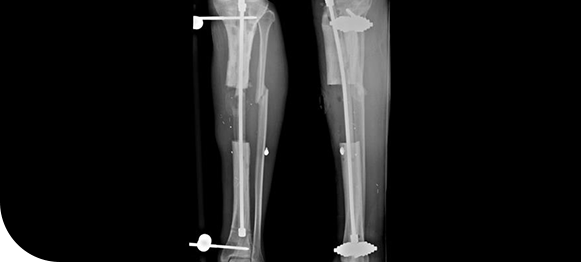

Nonunion

A nonunion occurs when a fractured bone fails to heal properly over time. Specialized orthopedic treatments are used to stimulate healing, restore bone stability, and prevent long-term pain or disability.

Know MoreBone Defect

Bone defects result from trauma, infection, or previous surgery, leaving gaps or weakened areas in the bone. Treatment focuses on reconstructing and strengthening the bone to restore structural integrity and function.